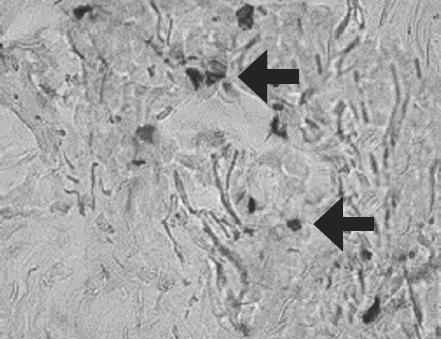

The results of three-year research on the use of allogeneic mesenchymal stem cells of adipose tissue (AMSCs) in the treatment of skin burns of II-III degree are presented. in a complex with wounds dressing of nanofibers chitosan and copolyamide, hyaluronic acid. It was found that with surgical necrectomy, introduction of AMSCs and substitution of defects with natural polymer coatings, the healing time is reduced by 89% (p < 0.05). Isolated administration of MSC reduces the healing period by no more than 5% (p > 0.05). The combined use of wounds dressings of nanofibers chitosan and copo lyamide with MSC accelerates the regeneration process by 26% (p < 0.05), with the introduction of AMSCs accelerating the development of granulation tissue by the fifth day of observation by 83% (p < 0.01). Joint use of wound coverings on the basis of hyaluronic acid with AMSCs is accompanied by an increase in the number of vessels of the microcirculatory bed in the defect area by 185% (p < 0.01). Clinical evaluation of the effectiveness of drugs with stem cells – a gel for topical application and a suspension of MSC LC for injection administration demonstrate their ability to optimize regeneration in the burn zone. Application of gel with AMSCs reduces the duration of epithelialization of border (dermal) burns by 2.2-2.4 times, with the final healing period being reduced by 59% (p < 0.01) and the suppuration frequency by 30% (p < 0.05). The introduction of a suspension of AMSCs into the zone of deep burn increases the frequency of engraftment of autografts, stimulates angiogenesis and proliferation of fibroblasts in the superficial and deep layers of the dermis. In the area of MSC administration, the LC perfusion level and the amplitude of blood flow fluctuation are twice as high as the values in the zones without the introduction of cells.